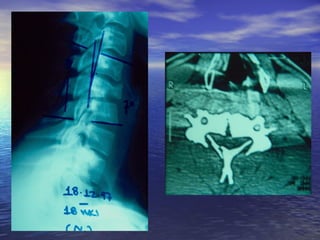

ΑΑππεειικκοοννιισσττιικκόόςς ΈΈλλεεγγχχοοςς

MM..RR..II..

ΕΕξξέέτταασσηη εεππιιλλοογγήήςς σσεε ππεερρίίππττωωσσηη

ννεευυρροολλοογγιικκήήςς σσηημμεειιοολλοογγίίααςς

ΑΑππεειικκοοννιισσττιικκόόςς ΈΈλλεεγγχχοοςς MM..RR..II.. ΕΕξξέέτταασσηη εεππιιλλοογγήήςς σσεε ππεερρίίππττωωσσηη ννεευυρροολλοογγιικκήήςς σσηημμεειιοολλοογγίίααςς